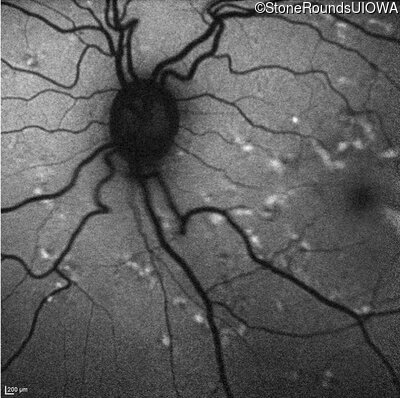

Infrared Fundus Photograph - Right - 20/20 -2

Exemplar